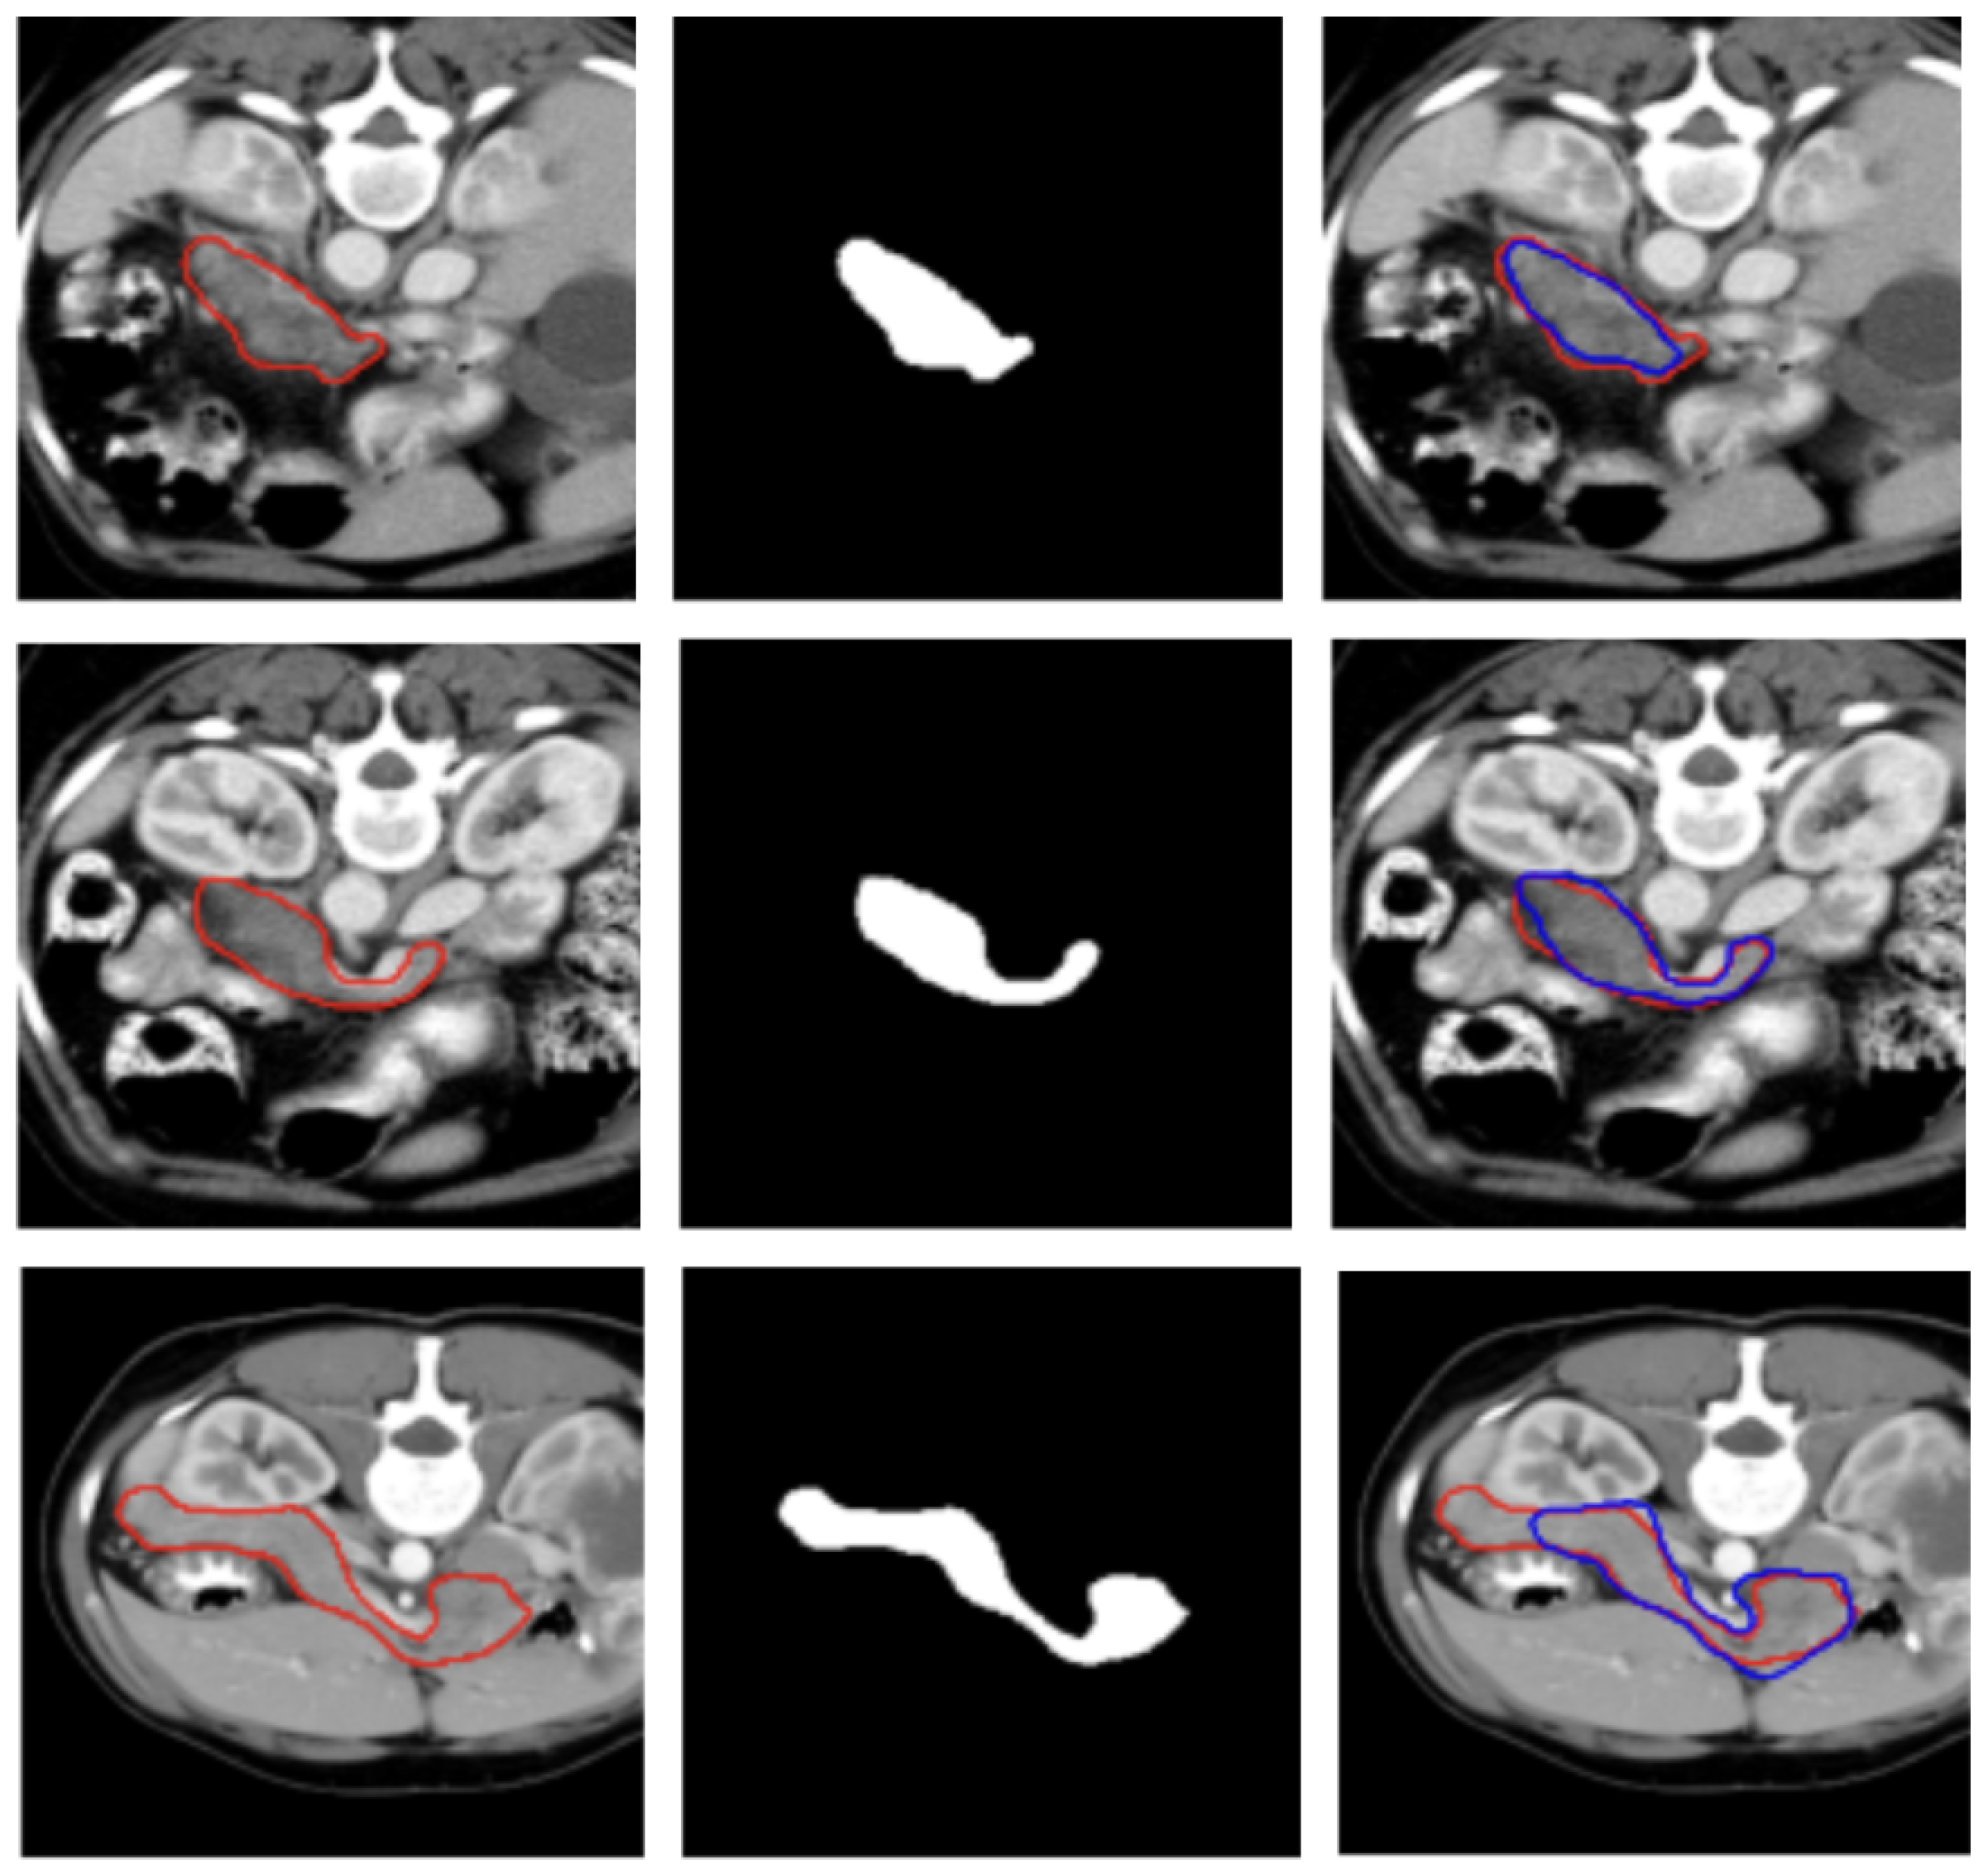

Three examples of segmentation obtained on test samples of the MSD dataset are illustrated in Figure 3.

Figure 3.

Visualization of two representative test samples from the MSD dataset showing: the input image with the pancreas ground truth overlaid as a red contour (left), the corresponding pancreas mask (center), and the output of the model overlaid to the input image as a blue contour (right). The first sample (first and second row) illustrates an easy case with clear organ boundaries and the second sample (bottom row) depicts a more challenging case with low contrast, yet the model still captures the main structure.

Figure 2 and Figure 3 show, qualitatively, the results of our attention-based 3D U-Net model trained on NIH and MSD datasets, respectively, with a combined Focal and Dice loss. The figures show across different sample cases, how the model successfully delineates the pancreas with high spatial accuracy, as demonstrated by the strong alignment between predicted and ground truth contours. The use of Dice loss contributed to the precise overlap in the segmented regions, while Focal loss improved the model sensitivity to challenging areas, especially along class boundaries where the pancreas is thin or adjacent to low-contrast structures. Notably, even in slices where the pancreas is partially obscured or appears small and fragmented, the model maintains accurate contour predictions. This suggests that the attention mechanism effectively focuses on relevant anatomical regions, suppressing background noise and enhancing feature discrimination.

These visual results support the quantitative performance of the model reported in Table 1 and Table 2 and demonstrate its ability to produce reliable and anatomically consistent pancreas segmentation in volumetric CT data.